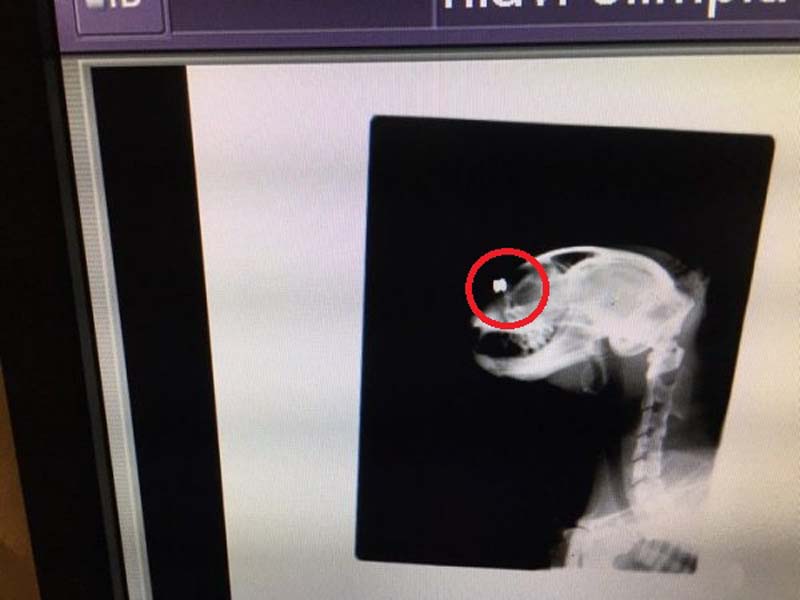

Ο Φιλοζωικός Σύλλογος Χανίων «Η ΠΡΟΣΤΑΣΙΑ ΤΩΝ ΖΩΩΝ» έφερε στη δημοσιότητα ακόμα ένα έγκλημα εις βάρος γάτας που συνέβη στο χωριό Βατόλακκος Χανίων στην Κρήτη. Η γάτα, που αν και βρέθηκε ετοιμοθάνατη στις 26 Δεκεμβρίου 2017, τελικά επέζησε, εντοπίστηκε με κρανιοεγκεφαλικές κακώσεις, με σπασμένη γνάθο ενώ οι ακτινογραφίες που έγιναν σήμερα έδειξαν ότι έχει δεκάδες σκάγια καραμπίνας στο κορμί της αλλά και πολλά σφαιρίδια αεροβόλου ένα εκ των οποίων είναι καρφωμένο στο κεφάλι της και προφανώς αυτό οδήγησε και στην τύφλωση της…

Ένα από τα μεταλλικά σφαιρίδια καρφωμένο στο κεφάλι του ζώου.

Ένα από τα μεταλλικά σφαιρίδια καρφωμένο στο κεφάλι του ζώου.

Επειδή δεν υπήρχε ακτινογραφία, αναλάβαμε τα περαιτέρω έξοδα και το ζώο μεταφέρθηκε στο κτηνιατρείο Καμπουράκη - Βαλυράκη, όπου από τις ακτινογραφίες διαπιστώθηκε ότι όλο το κορμάκι της ήταν διάτρητο από σκάγια, ενώ υπήρχε και ένα καρφωμένο ανάμεσα στα μάτια, που πιθανότατα προκάλεσε την τύφλωση στο άτυχο ζώο.